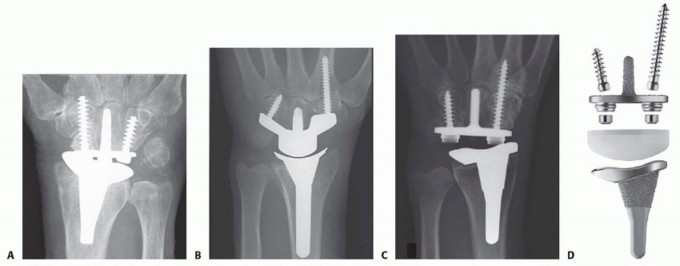

Surgical Management of Traumatic Conditions of the Elbow: Interposition Arthroplasty